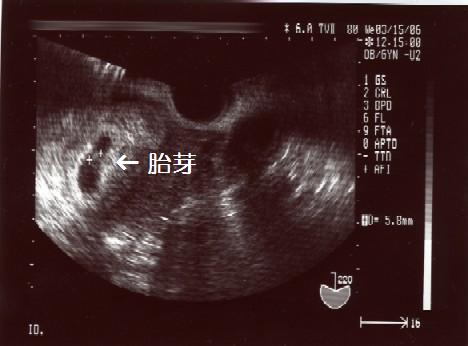

頭と尻尾の赤ちゃんが、うにょうにょ動いてました。(〃▽〃)

ダイゴローのときは、初めての診察は9週に入っていました。

今回の このコ より既に大きくて、心拍もはっきり確認でき、その日に母子手帳を貰いに行きました。

今回は、かなり初診が早かったんだなぁ~

なんか、子宮に痛みがあったので早く受診したんだけど…特に問題はないそう。